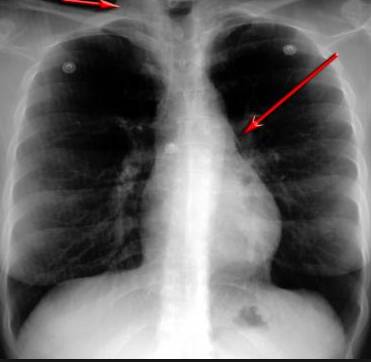

并且,因為呼吸系統(tǒng)結(jié)構(gòu)復(fù)雜,在體檢時醫(yī)生很難通過一種檢測手段,判定早期患者的病情。

把整個肺部看得清清楚楚!

使用這臺掃描儀,將直接把器官變成3D圖形!細(xì)微的毛細(xì)血管,幾毫米大的肺泡和支氣管,都將能看的一清二楚!

你的每一個氣泡,每一段支氣管,哪兒有病變都清清楚楚的將展示在醫(yī)生面前!

也就是說在一切都還沒開始惡化前,把這些有問題的器官組織都暴露的一清二楚:

不同于CT掃描,需要從同一角度,拍下無數(shù)張器官二維圖,從而搭建3D器官結(jié)構(gòu)圖那般費時費力。

4D掃描儀將直接從不同角度,同時對人體器官進(jìn)行掃描,然后通過計算機算法進(jìn)行快速成像。CT需要花幾小時才能完成的工作,

4D掃描將在幾秒內(nèi)完成!

可是現(xiàn)在他們不但能看到整個肺部的3維結(jié)構(gòu)圖。還能看到空氣進(jìn)入人體后的所有微小變動!